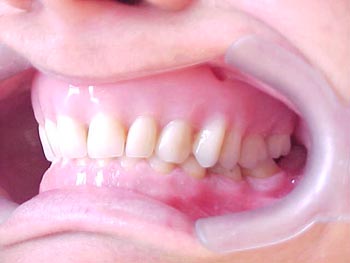

Diagnóstico preliminar das principais ocorrências: Prótese total na maxila em articulação com dentição natural inferior, apresentando acentuado trespasse horizontal (mordida profunda) e inclinações linguais generalizadas, com ausência do primeiro molar inferior esquerdo.

Plano de tratamento: 1) Tratamento ortodôntico para a mandíbula, com o propósito de reverter (alinhar e nivelar) a má-oclusão descrita acima; 2) Implantes maxilares como base de sustentação de prótese fixa, com gengiva artificial para compensar a reabsorção óssea ocorrida ao longo dos anos; 3) Reposicão do elemento ausente na mandíbula com implante e coroa metalo-cerâmica; 4) Próteses unitárias diversas sobre raízes naturais; 5) Reanatomizações e restaurações diversas em resina composta direta.

Confirmação da inclinação lingual generalizada em todos os elementos dentários